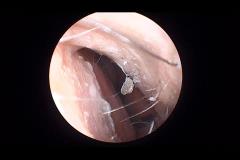

Frontal Sinus Case 2-15-2012

2/16/2012 12:23:28 PM

by Mac Barry

3326

1

0